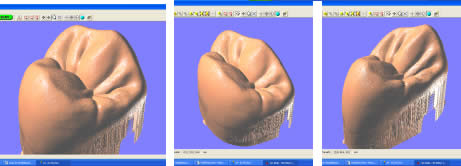

Introducción.- En oclusión, existen varios campos de aplicación básica para la digitalización. Hablamos, preferentemente, de la digitali- zación tridimensional. Recordemos que esta palabra es sinónimo de medición y –como tal- auxilio en esta rama odontológica tan necesitada de precisión. La digitalización tridimensional consistirá en el registro de la posición espacial, de un finito número de puntos, determinando sus coordenadas -x,y,z-. A menor distancia entre cada punto se conseguirá como resultado un objeto virtual con mayor detalle, coincidente con el real. Con cada triada se podrá formar una superficie, que continuada con la generada por el resto de la malla de puntos, completarán la forma del objeto. Este es el origen de donde partimos para establecer el concepto básico de las revolucionarias aplicaciones 3D. Se parte así del denominado escaneado tridimensional: Escaneado Superficial de un objeto real -> “Nube de Puntos” -> “Malla de Alambre” -> Superficie del Objeto Virtual. Con los modelos dentarios, impresiones o registros de oclusión, virtuales (en la pantalla del ordenador), realizaremos ahora, mediante un programa informático, la manipulación simulada, mediante computadora, para la realización del estudio y diseño de la oclusión. La Oclusión Computarizada (OC) –dentro de la más amplia Odontología Computarizada- comprende, hoy, fundamentalmente, tres fines: 1º)- El Estudio, Diagnóstico y Plan de Tratamiento Asistidos por Ordenador. 2º)- El Encerado Computarizado. (Por RP –Rapid Prototyping-, Prototipado Rápido, o por CAM –Computer Assisted or Aided Machining or Manufacturing-, Maquinado Asistido o Ayudado por Computador). 3º)- La Restauración y Confección de Prótesis Computarizada. (Por CAD-CAM, -Computer Assisted Design – Computer Assisted Manufacturing-, Diseño y Fabricación Asistidas por Computador). La Odontología Computarizada tiene entre sus numerosas secciones, ésta de oclusión, considerada primordial en el trabajo clínico habitual, desde la que nos relacionamos con la ortodoncia, cirugía implantológica, tecnología protésica y prostodoncia. Cada uno de los citados fines de la OC necesita partir de un escaneado tridimensional de los objetos a tratar: elementos del sistema dentario (arcadas) –de forma directa, en la misma boca del paciente-, o modelos dentales obtenidos por una impresión material de éstas y su posterior escaneado –o forma indirecta, fuera de la boca del paciente-. El escaneado se puede realizar con variados dispositivos, resultando procedimientos de distintos tipos y con diferentes características, clasificados simplificadamente como: A) Escaneado de contacto, háptico: B) Escaneado sin contacto: Tomando una imagen del objeto, marcado por líneas o cuadrículas luminosas proyectadas sobre su superficie, que se deforman con ella, analizándose luego digitalmente. El escaner se considera aquí un analizador trigonométrico del objeto, que registra su imagen, marcada mediante un rayado por luz –normalmente láser- (que permite, mediante software, obtener las coordenadas espaciales de multitud de puntos, que son agrupados en unidades de tres, constituyendo los vértices de una superficie triangular, que sumándose a las vecinas, llegarán a representar la envuelta completa del objeto y así su forma volumétrica o tridimensional). C) Combinado. Externo e Interno. Los escáneres suelen resultar, actualmente, poco económicos, y aunque van decreciendo en coste, están –para estas fechas- en un nivel que suele partir como mínimo de los 8.000 euros; siempre dependiendo del procedimiento de registro empleado, tamaño y precisión del escaneado. Existen: A) aparatos integrados en sistemas dentales, desarrollados específicamente para nuestro campo, de comprobada eficacia y de alto coste económico; B) dispositivos de uso general, aplicables a los propósitos de la odontología, de complicada adaptación pero de muy bajo coste relativo; C) múltiples posibilidades para la construcción de un escaner propio, casero y económico, que pueda, con suficiente experiencia, llegar a funcionar para uso profesional, gracias a la existencia de suficiente información de la tecnología empleada, ampliamente divulgada y de fácil desarrollo; útiles para fines diagnósticos. En oclusión necesitamos el 3D, pero también el 4D. Sumamos aquí a las tres coordenadas espaciales de cada punto del objeto, otra más, la cuarta dimensión: el tiempo. Dado que un objeto móvil, lo es por la temporalidad de sus posiciones en el espacio. Así se registrarán y analizarán digitalmente los movimientos mandibulares para conseguir la articulación y reproducción de la función masticatoria. Para esto se han aplicado determinados registros, mediante sensores de posición o por receptores de actividad muscular, como los electromiógrafos, o el más específico articulador virtual, del que se encuentran diferentes productos de software, englobados –como complemento necesario- en los programas que acompañan a los distintos sistemas de cad-cam dental. Desde el escaneado, o transformación u obtención del objeto real en cuerpo 3D, numérico, adquirido para ser estudiado y manipulado de forma digital, virtual, en el computador, continuamos con otras vías, ahora posibles, de enorme potencial, desde el estudio y planificación a la fabricación protésica. Así van a ser expuestas a continuación: A) La planificación; B) el encerado; y C) la fabricación. A) -Estudio, Diagnóstico y Plan de Tratamiento Asistidos por Ordenador. La planificación de la rehabilitación oclusal, puede iniciarse: A-1) Por Registro Estático Morfológico Computarizado, del aparato estomatognático y sistema dentario. Que puede realizarse: I) A partir de Escaneado Extraoral. I-a) Escaneado Volumétrico (CT–tomografía computarizada-) (O mejor, CBCT –tomografía computarizada de haz cónico-, de menor radiación y coste, con aparatos diseñados específicamente para uso dento-máxilo-facial ). I-b) Escaneado Superficial –de los modelos de estudio- y Registros Oclusales-. II) A partir de Escaneado Intraoral. II-a) Escaneado Volumétrico (CT local, o CBCT local, que se están desarrollando para aplicación retroalveolar). II-b) Escaneado Superficial –de las caras oclusales del sistema dentario-. A-2) Por Registro (Estático Morfológico Computarizado) de Huellas de Oclusión (o Registros Oclusales), para análisis de contactos intermaxilares, estáticos -y menos o indirectamente los movimientos mandibulares-. Mediante escaneado superficial de registros, sus modelos 3D, y combinación o no, con el Papel de Articular Electrónico (T-Scan). A-3) Por Registro Dinámico Funcional (fisiológico) Computarizado: I) Registro Computarizado (Integrado) de los Movimientos Mandibulares –electropantográfico o cinematográfico-. Por sensores o marcadores de posición. II) Registro Computarizado (Integrado) de la Función Muscular –electromiográfico-. A-4) Por Integración Informática de varios de los Registros citados. B) -Encerado Computarizado. Es el modelado o diseño virtual en la pantalla del ordenador y su realización en material de patronaje (como la cera u otro de similar; económico, modificable, transformable y rápido), que puede realizarse por: B-1) Por RP –prototipado aditivo- o B-2) por CAM –maquinado sustractivo-. Como pensamos en el concepto clásico, la realización de un encerado diagnóstico es clave para una rehabilitación oclusal correcta. Además el encerado servirá para la confección de: a) una posible férula radiológica y quirúrgica, b) una referencia para el tallado, la prótesis o rehabilitación temporal y el patrón para la definitiva. Se llevará a cabo, en dos etapas: 1ª) Etapa de creación del patrón. Elaboración virtual en la pantalla del ordenador. Necesitando el software apropiado, CAD. 2ª) Etapa de confección. Elaboración Real, mediante RP o CAM. 1ª) La etapa de creación virtual del patrón en la pantalla del ordenador, mediante un programa informático de diseño y manejo de objetos tridimensionales, (siempre partiendo de un registro previo, como el escaneado de los modelos), puede facilitarse con varias herramientas para: -Elaboración Virtual por Adición. 2ª) La etapa de confección, o elaboración real, mediante RP o CAM. -Confección por RP (Rapid Prototyping) –Prototipado Rápido-, de adición o construcción capa a capa, añadiendo una sustancia que se endurece, aumentando su nivel en superficie. La elaboración real por adición, es posible en un variado –pero limitado- tipo de materiales. -Confección por CAM (Computer Aided Machining) –Maquinado o Tallado Asistido por Ordenador-, de eliminación de sustancia o esculpido en un bloque sólido. La elaboración real por sustracción, es posible en un numeroso -y casi ilimitado- tipo de materiales. Existen gran cantidad de dispositivos que consiguen la fabricación y consecución física de un encerado real, a partir de su elaboración virtual, desde un escaneado y su diseño computarizado. Todos los sistemas denominados de cad-cam dental, en general, aunque no estén espe- cialmente dispuestos para ello, pueden dedicarse a este propósito; simplemente colocando un material de patronaje, como la cera, en lugar del material con el que se constituirá la prótesis definitiva. Pero, existen –también- sistemas espe- cialmente configurados para el trabajo en material de diseño, normalmente: ceras, resinas o compuestos, es lo que se denomina prototipado rápido (rapid prototyping). En la industria general, la fabricación de cualquier objeto en serie, requiere de estos procedimientos en las primeras etapas de elaboración para su producción. La más económica y reducida Impresora 3D o Sistema de Prototipado Rápido, que puede confeccionarnos unos maxilares, a partir de la tomografía, o un encerado diagnóstico, según el software disponible. Su precio actual 45.000 Euros. C) -Restauración y Confección de Prótesis Computarizada. (Por CAD-CAM). Es el modelado o diseño virtual en la pantalla del ordenador y su realización en material definitivo (como porcelana, titanio, aleación preciosa, u otro similar); poco económico, difícilmente o no modificable, ni transformable y que requiere de un tiempo adecuado, mucho mayor que el requerido para la confección del patrón de material plástico. Esto puede realizarse por numerosos dispositivos. Existen gran variedad de sistemas para el diseño y confección de restauraciones y prótesis. Son los denominados gene- ralmente SISTEMAS DE CAD-CAM DEN- TAL (Dental Cad-Cam System): (Entre estos sistemas encontramos los que también pueden planificar el tratamiento restaurativo y realizar el encerado diagnóstico con diseño y confección de un patrón oclusal; como hemos referido antes). Históricamente estos sistemas comenzaron con la década de los setenta -en 1971, con el Holodontography-Altschuler System-, y con el Sopha System de Duret, progresando enormemente hasta comienzos de los noventa. Durante esos veinte años, se potenció su desarrollo con el siguiente hito histórico que los encumbró, en su segunda década, por la aparición de los principales impulsores del cad-cam clínico comercializable -Mörmann y Brandestini, en 1981-, denominado Sistema Cerec. También se establecieron los principios de estos dispositivos con el DCS Dental System, el CAP System, el Minnesota-Rekow System, el Nissan Cad/Cam System, Automill y Microdenta System. El culmen del progreso se alcanzó a mediados de los noventa, con sistemas ampliamente comercializados y evolucionados hasta hoy: Procera, DCS Dental, o Cicero. En los siguientes diez años, se continuó perfeccionando los sistemas citados; hubo algunos sistemas no comerciales o de escasa difusión, o distribuidos moderadamente; repre- sentando un período hasta el 2000, con una pequeña depresión, en los años medios, por el declive en la extensión de estos productos, en relación al extraordinario futuro que se les auguraba, motivada por el alto coste de los equipos y las limitaciones en su potencia digital, en el que –aún y así- aparecieron sistemas como: Belledent, Cadim, Dentscan, CCD System, Cynovad, Digident-Girrbach, Decim y Etkon. La segunda revolución para la odontología por cad-cam se produjo con el comienzo del siglo. Ampliándose enormemente la cantidad de sistemas y alentándose una explosión del trabajo digital en odontología, con: Cercon-Degussa, Lava-3M-Espe, Cad-Esthetics System-Ivoclar, DDS, GC-Dental, Everest-Kavo y Bego. En estos momentos el futuro de la odontología se encuentra inexorablemente unido a estos aparatos. Para el clínico o el laboratorio dental es hoy imprescindible contar con ellos. Siguen nuevas apariciones, como el sistema Hint-Els, o el Evolution-4D, similar al Cerec, que fue el pionero, pero que todavía, a la fecha, se mantiene como el más versátil, modulable y práctico, con progresos como el facilitado trabajo de diseño tridimensional o el nuevo escaneado extraoral independiente. Los sistemas de cad-cam, están integrados por: un escaner que digitaliza el objeto dental, un ordenador con el software adecuado para el diseño virtual, y una máquina de tallado para la fabricación del objeto diseñado en un material determinado. Una relación actualizada, de gran número de los sistemas existentes se encuentra en “Aktuelle CAD/CAM Systeme”, en http://www.tu-dresden.de/medprothetik/computerzahn/CAD-CAM-Systeme.htm Factores clave en la Oclusión Computarizada-. La digitalización del estudio, diagnóstico y tratamiento de la oclusión, como la construcción o restauración de un sistema dentario óptimo para la correcta función masticatoria del aparato estomatognático, pretende facilitar y generalizar la excelencia en el trabajo clínico. Es una aplicación de preferencia informática porque pueden manejarse gran cantidad de datos, mediciones, relaciones geométricas, unidas a la tridimensionalidad y la movilidad de sus elementos, de una forma racional, lógica y científicamente fundamentada, aún partiendo de concepciones filosóficas o criterios sujetos a distintas escuelas de oclusodoncia. La digitalización de la oclusión pude llevar- nos a despejar supuestos sin evidencia científica, de la que adolece sectorialmente nuestro arte. Tenemos suficientes fórmulas, reglas y relaciones numéricas, aportadas por numerosos autores, que tienen que se recopiladas y que pueden así ser aplicadas. Yá que la digitalización recoge todos los datos métricos y posicionales (coordenadas de cada punto, con su x,y,z), del sistema dentario, se pueden establecer fórmulas matemáticas para que -siendo la z la determinante de la altura de un punto en el espacio-: una z máxima, de una pieza mandibular, esté más o menos próxima a una z mínima de una pieza maxilar; que un punto (de cúspide) -con una determinada x,y- maxilar, coincida con otro –con la misma x,y- mandibular, pero con distintas aunque casi idénticas z, dándose el contacto oclusal. Y de esta forma, con sucesivas relaciones (matemáticas) se construiría una oclusión tendente a la excelencia; matemáticamente desarrollada. Así podría confeccionarse, automáticamente, una oclusión geométrica, dando, por ejemplo, solamente: la posición base de cada pieza, la x,y de las cúspides de una hemiarcada, y la altura de su plano oclusal, y automáticamente se generarían las cúspides agonistas y antagonistas, y la morfología dental completa de ambas arcadas. Se tendrían que añadir los datos correspondientes a los dientes anteriores, a las ATMs y las fórmulas de relación de las pendientes. Distintos autores han desarrollado relaciones métricas en oclusión. Algunos han simplificado el proceso, como partida, para ir añadiendo variantes; así, pueden usarse valores standard, normales, del ángulo cuspídeo para fabricar la morfología oclusal en CAD/CAM, -cuando la creación del esquema oclusal es de novo-, según Hobo y Takayama; y el uso de varios valores fijos de partida, universalmente aceptados, en lugar de la medida directa de la pendiente condilar es, según los mismos autores, muy importante en el desarrollo extenso de los sistemas de CAD/CAM. Así, el procedimiento de «twin-stage» propuesto por estos autores, en su libro “Oral Rehabilitation”, proporciona una solución en la producción de una oclusión dinámica tridimensional para el CAD/CAM. Otra técnica, consiste en el encerado virtual, mediante un modelado CAM, siguiendo las etapas de Shillimburg, o Kuwata, elaborando paso a paso la morfología oclusal, orientada a su enfrentamiento con el antagonista, encaminando los volúmenes cuspídeos como en el encerado progresivo clásico, gota a gota. Se realizaría su construcción virtual en la pantalla del ordenador, pudiendo estar facilitada su manipulación, mediante “espátulas de encerado virtual”, utilizando los digitalizadores de brazo articulado, con los que se pueden disponer los volúmenes necesarios, en la posición espacial que se desee. No obstante, el modelado dental se puede realizar siempre, aunque sea a través del clásico ratón del ordenador, de forma virtual, con la imagen tridimensional en la pantalla, utilizando diferentes procedimientos, con el software adecuado: A) Automático, a partir de las reglas dentométricas, odontométricas y cefalométricas, relacionadas con la gnatología, tomando previamente los valores claves necesarios del paciente. B) Mediante diseño de la anatomía con trazado de los perfiles, líneas y curvas, que van a definir las superficies dentales. Trabajando bidimensionalmente, en base a cortes de la estructura a construir, que manipulada variando sus dos dimensiones, va a corresponderse con la morfología dental tridimensional, al establecerse un área de influencia y cambio en los cortes vecinos, y así alterándose el volumen dental completo. Este era el procedimiento de variación anatómica utilizado, durante dos décadas con el Sistema Cerec (el Cerec 1, Cerec 2 y Cerec 3), hasta la llegada del Cerec 3D. C) Mediante copiado de la cara oclusal ideal, realizada previamente en cera u otro material real, del diente, su registro oclusal o su antagonista, en el concepto original del Sistema CEREC, de construcción oclusal mediante Correlación –copiando un encerado previo- o Función –correspondiendo automáticamente a la cara oclusal del antagonista-. D) Mediante selección de dientes, individuales o en grupo (incisivos, caninos, premolares, molares, arcadas, hemiarcadas, sistema dentario, maxilares o mandibulares), de entre un grupo de archivos de modelos dentales tridimensionales virtuales, como una librería de objetos 3D. Como en la selección de las tablillas de dientes para la confección de las prótesis completas. Escogiendo tamaño y forma. Colocando cada pieza o bloque en su lugar, con la disposición espacial y oclusal correspondiente. E) Mediante la misma selección, antes citada, seguida luego de una transformación, como estiramiento o estrechamiento, u otras variaciones morfológicas, con las herramientas de edición del programa informático, hasta conseguir la oclusión que se pretende. F) Mediante encerado virtual, de adición progresiva de volúmenes anatómicos, en el concepto clásico de encerado gota a gota, con la metódica de P. K. Thomas, para restauraciones parciales, o de Kuwata, para rehabilitaciones extensas. El método de encerado es el que nos permitirá la construcción de una oclusión individualizada. Pero la necesidad de utilización de un articulador es evidente. Es presumible que se desarrollen nuevos instrumentos para la perfección de la oclusión computarizada, semejantes a los articuladores mecánicos tradicionales. Serán los denominados articuladores virtuales, (VA –Virtual Articulator-), o simuladores digitales de la articulación oclusal, consistentes en un programa informático, capaz de relacionar los modelos virtuales, permitiendo movimientos similares a los naturales del paciente: es la aplicación de la tecnología de la realidad virtual a la oclusión (VR –Virtual Reality-). Esto es lo que nos permitirá pasar de la fórmula empleada generalmente para el modelado oclusal, que suele ser estática y referida a un registro de las superficies antagonistas, a un sistema experto que reproduzca la relación completa de ambas arcadas, las articulaciones, y su combinación con los movimientos masticatorios: realizando la dinámica mandibular. Hoy en la mayoría de los sistemas de cad-cam, los trabajos oclusales se realizan, extensamente, basados sólo en el enfrentamiento con el antagonista, sin tener en cuenta la movilidad mandibular, las guias condilares o anteriores. Es como si realizásemos un encerado oclusal sin tener en cuenta los determinantes anteriores y posteriores, y trabajásemos en un articulador, no ajustable, o simplemente en un Oclusor o Verticulator, sin giro de cierre ni desplazamientos horizontales.El articulador virtual, por software, para el diseño oclusal en la pantalla del ordenador, aún no es empleado de forma generalizada en estos sistemas, pero ya se encuentran como aplicaciones en algunos de ellos. Uno de los pioneros se utiliza en el sistema Cynovad. Aquí, directamente relacionado con la confección de un encerado oclusal. Otros dispositivos electrónicos y digitales, de registro por ordenador, que podrían combinarse con la construcción plástica de la oclusión, en cera u otro material, solo se están utilizando para diagnóstico, o como complementos a articuladores mecánicos sofisticados; así podemos encontrar programas como Rosy32 Robot System (Diagnostic Articulator), de registro dinámico, el VirtSet, de diagnóstico y predicción oclusal-ortodóntica, o el ArtiKulator-Software (ver ArtiDemo), de programación virtual de un articulador, con elección del equivalente mecánico real (Sam, Artex, Kavo,…). Entre éstos, el sistema más completo desarrollado, con escaneado de modelos y registros, y correspondencia con la dinámica mandibular, obtenida por un arco facial cinemático, con sensores de posición y movimiento, es el DentCAM.Para clasificar los instrumentos de oclusión, consideramos muy completa la clasificación de los articuladores mecánicos, desarrollada en The International Workshop Occlusion, de 1972, University of Michigan: 1) Clase I – Sujetadores simples de modelos. Subdivisión A (Con movimientos verticales; Corelator, Verticulator). Subdiv. B (Con articulación de bisagra sin desplazamientos horizontales; Centric Relator). Conclusiones (parciales para esta primera parte).- El articulador virtual podría establecerse a partir del escaneado de un articulador mecánico seleccionado, a partir de un modelo construido íntegramente por CAD de forma virtual, o –idealmente- a partir de un patrón anatómico, individual, a partir de la radiología tridimensional (como la Tomografía Computarizada). A estas estructuras se les sumarán los datos necesarios para la función: relación intermaxilar –estática- (oclusal) y relación cráneo-mandibular dinámica (pendiente condílea y Bennett), con ayuda también del registro de la actividad muscular (electromiografía). A la clasificación de los articuladores antes expuesta, le podemos añadir ahora el Tipo V, constituido por los Articuladores Virtuales, o instrumentos informáticos que pueden reproducir la oclusión dental en el ámbito de la realidad virtual, que se desarrollan como programas informáticos concretos, de muy variada composición en sus elementos de software, y distintos por los diferentes tipos de registros que necesitan para su efectiva y precisa actuación. Dentro de este V grupo, a su vez, podríamos –paralelamente a la clasificación de los articuladores mecánicos-, establecer tantas subclases como las de los tipos y subclases de aquellos. Así habría de clase I, como ocurre mayoritariamente en los sistemas de Cad-Cam dental actuales, cuando utilizamos modelos dentales 3D y registros estáticos de antagonistas. Es éste el cambio que se experimentará en los próximos años, en la Oclusión Computarizada: la utilización generalizada de Articuladores Virtuales de clase III y IV. Bibliografía Cooper BC. Parameters of an optimal physiological state of the masticatory system: the results of a survey of practitioners using computerized measurement devices. Cranio. 2004 Jul;22(3):220-33. Reiss B. Occlusal surface design with Cerec 3D. Int J Comput Dent. 2003 Oct;6(4):333-42 Petrie CS, Woolsey GD, Williams K. Comparison of recordings obtained with computerized axiography and mechanical pantography at 2 time intervals. J Prosthodont. 2003 Jun;12(2):102-10. Kojima T, Sohmura T, Nagao M, Wakabayashi K, Nakamura T, Takahashi J. A preliminary report on a computer-assisted dental cast analysis system used for the prosthodontic treatment. J Oral Rehabil. 2003 May;30(5):526-31 Bernhardt O, Kuppers N, Rosin M, Meyer G. Comparative tests of arbitrary and kinematic transverse horizontal axis recordings of mandibular movements. J Prosthet Dent. 2003 Feb;89(2):175-9 Tsai HH. A computerized analysis of dental arch morphology in early permanent dentition. ASDC J Dent Child. 2002 Sep-Dec;69(3):259-65, 234 Ferrario VF, Sforza C, Serrao G, Schmitz JH. Three-dimensional assessment of the reliability of a postural face-bow transfer. J Prosthet Dent. 2002 Feb;87(2):210-5. Kerstein RB. Current applications of computerized occlusal analysis in dental medicine. Gen Dent. 2001 Sep-Oct;49(5):521-30 Kerstein RB, Wilkerson DW. Locating the centric relation prematurity with a computerized occlusal analysis system. Compend Contin Educ Dent. 2001 Jun;22(6):525-8, 530, 532 passim; quiz 536. Sohmura T, Kojima T, Wakabayashi K, Takahashi J. Use of an ultrahigh-speed laser scanner for constructing three-dimensional shapes of dentition and occlusion. J Prosthet Dent. 2000 Sep;84(3):345-52. Kerstein RB. Computerized occlusal management of a fixed/detachable implant prosthesis. Pract Periodontics Aesthet Dent. 1999 Nov-Dec;11(9):1093-102 Tarantola GJ. A computerized model for teaching various methods of positioning the condyles to centric relation. Gen Dent. 1999 May-Jun;47(3):308-12 Gsellmann B, Schmid-Schwap M, Piehslinger E, Slavicek R. Lengths of condylar pathways measured with computerized axiography (CADIAX) and occlusal index in patients and volunteers. J Oral Rehabil. 1998 Feb;25(2):146-52 Tamaki K, Celar AG, Beyrer S, Aoki H. Reproduction of excursive tooth contact in an articulator with computerized axiography data. J Prosthet Dent. 1997 Oct;78(4):373-8 Garcia Cartagena A, Gonzalez Sequeros O, Garrido Garcia VC. Analysis of two methods for occlusal contact registration with the T-Scan system. J Oral Rehabil. 1997 Jun;24(6):426-32 Matsui Y, Ohno K, Michi K, Suzuki Y, Yamagata K. A computerized method for evaluating balance of occlusal load. J Oral Rehabil. 1996 Aug;23(8):530-5 Giddon DB, Sconzo R, Kinchen JA, Evans CA. Quantitative comparison of computerized discrete and animated profile preferences. Angle Orthod. 1996;66(6):441-8 Matsui Y, Neukam FW, Wichmann M, Ohno K. A computerized method for evaluating distribution of occlusal load on implant-supported fixed cantilever prostheses. Int J Oral Maxillofac Implants. 1996 Jan-Feb;11(1):67-72 Hayashi T, Saitoh A, Ishioka K, Miyakawa M. A computerized system for analyzing occlusal relations during mandibular movements. Int J Prosthodont. 1994 Mar-Apr;7(2):108-14 Maness WL. Computerized occlusal analysis. J Can Dent Assoc. 1993 Aug;59(8):701-2 Edwards CL, Richards MW, Billy EJ, Neilans LC. Using computerized cephalometrics to analyze the vertical dimension of occlusion. Int J Prosthodont. 1993 Jul-Aug;6(4):371-6 Giannazzo E, Leonardi R, Scivoli M, Rapisardi CB, Vassallo V. [Computerized parametrization in orthognathodontics] Boll Soc Ital Biol Sper. 1993 Jun;69(6):373-9 Harvey WL, Osborne JW, Hatch RA. A preliminary test of the replicability of a computerized occlusal analysis system. J Prosthet Dent. 1992 May;67(5):697-700 Boening KW, Walter MH. Computer-aided evaluation of occlusal load in complete dentures. J Prosthet Dent. 1992 Mar;67(3):339-44 Reza Moini M, Neff PA. Reproducibility of occlusal contacts utilizing a computerized instrument. Quintessence Int. 1991 May;22(5):357-60 Harvey WL, Hatch RA, Osborne JW. Computerized occlusal analysis: an evaluation of the sensors. J Prosthet Dent. 1991 Jan;65(1):89-92 Palano D, Molinari G, Salvo C. [Electromyography and computerized magnetic gnathokinesiography in the diagnosis and therapy of craniomandibular disorders] Minerva Stomatol. 1990 Dec;39(12):977-87